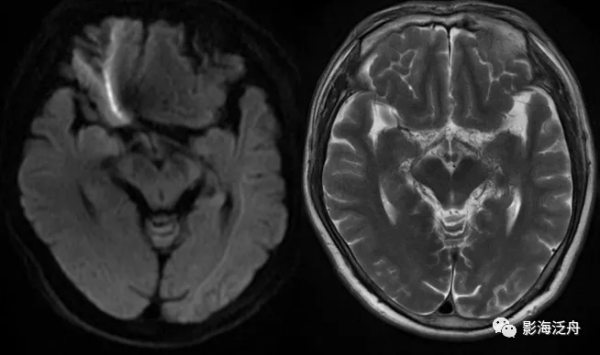

病例二:患者女,78歲,頭暈1周,無頭痛、惡性嘔吐等症狀,既往有胃CA手術史和糖尿病、高血壓等病史。

病例二:左側前交通動脈動脈瘤。動脈瘤瘤體顯示清晰,呈流空改變,內見斑片狀T2WI稍高訊號影,可能是湍流造成的。如果腦子裡完全沒有去觀察顱內血管的意識,那就很容易漏診。